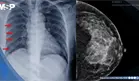

Se reposicionó a la paciente e inició RCP diez minutos después del evento. La ecocardiografía transesofágica durante la reanimación demostró cierre valvular aórtico, dilatación marcada del ventrículo derecho y ausencia de émbolos en arteria pulmonar, sugiriendo insuficiencia ventricular derecha aguda. El ritmo cardíaco inicial fue fibrilación ventricular refractaria a epinefrina y vasopresores.

La tomografía computarizada postoperatoria inmediata descartó embolia pulmonar pero reveló extravasación de cemento óseo más allá de la cavidad medular femoral.

La dilatación ventricular derecha sin evidencia tromboembólica en ecocardiografía y tomografía confirma este mecanismo.